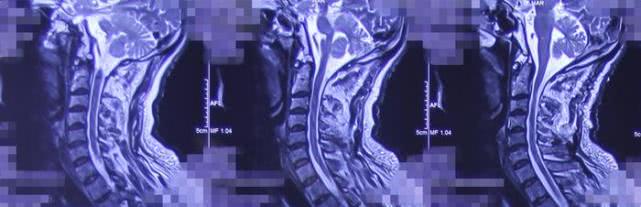

术后影像学资料

颈1-2

胸5-7